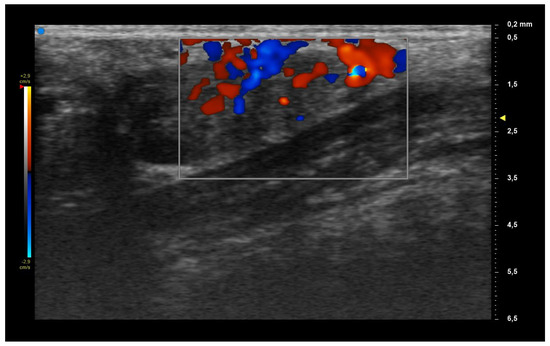

| UHFUS Characteristics | Sicca Syndrome (n = 4) | Parotitis (n = 2) | Non-Sicca, Non- Parotitis (n = 6) | Total (n = 12) |

|---|---|---|---|---|

| Grade 1 | 3 (75%) | 1 (50%) | 4 (67%) | 8 (67%) |

| Grade 2 | 0 (0%) | 1 (50%) | 1 (17%) | 2 (17%) |

| Grade 3 | 1 (25%) | 0 (0%) | 1 (17%) | 2 (17%) |

| Mild vascularization | 1 (25%) | 1 (50%) | 1 (17%) | 3 (25%) |

| Moderate vascularization | 3 (75%) | 1 (50%) | 5 (83%) | 9 (75%) |